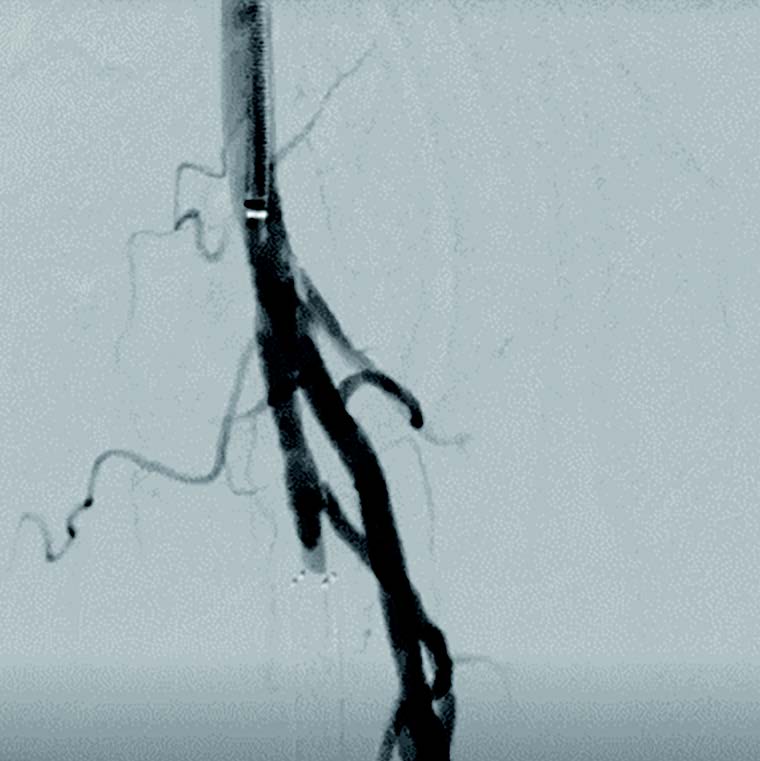

本症例は、初回治療2年後フォローアップ時のエコー所見から、DESの中枢および末梢の病変が閉塞の原因となった可能性が高い。同部位はDCBおよびDESで治療されているにもかかわらず、2年で再狭窄を呈していることから、drug technologyを用いたバルーンおよびステントでの治療は許容できないと判断した。BMI 31.9の肥満であったため右総大腿動脈より対側山越アプローチとした。6 Fr 45 cmガイディングシース + 5.5 Frシースバックアップ下に血管内超音波(IVUS)ガイドで臨んだ。エコー所見どおりDESの中枢および末梢病変は非常に強固であったため、ガイドワイヤー(40 g)で通過した。DES内の病変は非常に柔らかく、ガイドワイヤー(1 g)で通過、DCBのステント内閉塞はガイドワイヤー(15 g)を用い、IVUS下に確実に真腔内で通過した。0.014 inchガイドワイヤーの場合、ガイドワイヤーはステントストラットを容易に通過する。そのため、複数方向からの透視やIVUSを用いることで、確実にステント内を通過していることを確認することが必要となる。また、ステント内はhealthy landingではないことから、確実に前回のステントを最低1 cm以上越えて留置すべきである。DESの再狭窄は、culprit以外が柔らかい赤色血栓であることが多く、この症例もガイドワイヤーの感覚から同様の所見が疑われた。末梢塞栓予防に造影カテーテルによる可及的血栓吸引を行い、バルーン4.0 mm × 300 mmで前拡張をした。末梢病変はバイアバーン® ステントグラフト6 mm × 150 mmを留置、中枢は左浅大腿動脈起始部から10 mmのhealthy landingが残存していたため、同部位よりステントグラフト6 mm × 150 mmを留置した(図1)。高耐圧バルーン6.0 mm × 150 mmで後拡張を行い(図2、図3)、十分にgainを確保し良好なflowで終了した。治療時間は40分、造影剤使用量は70 mL であった。